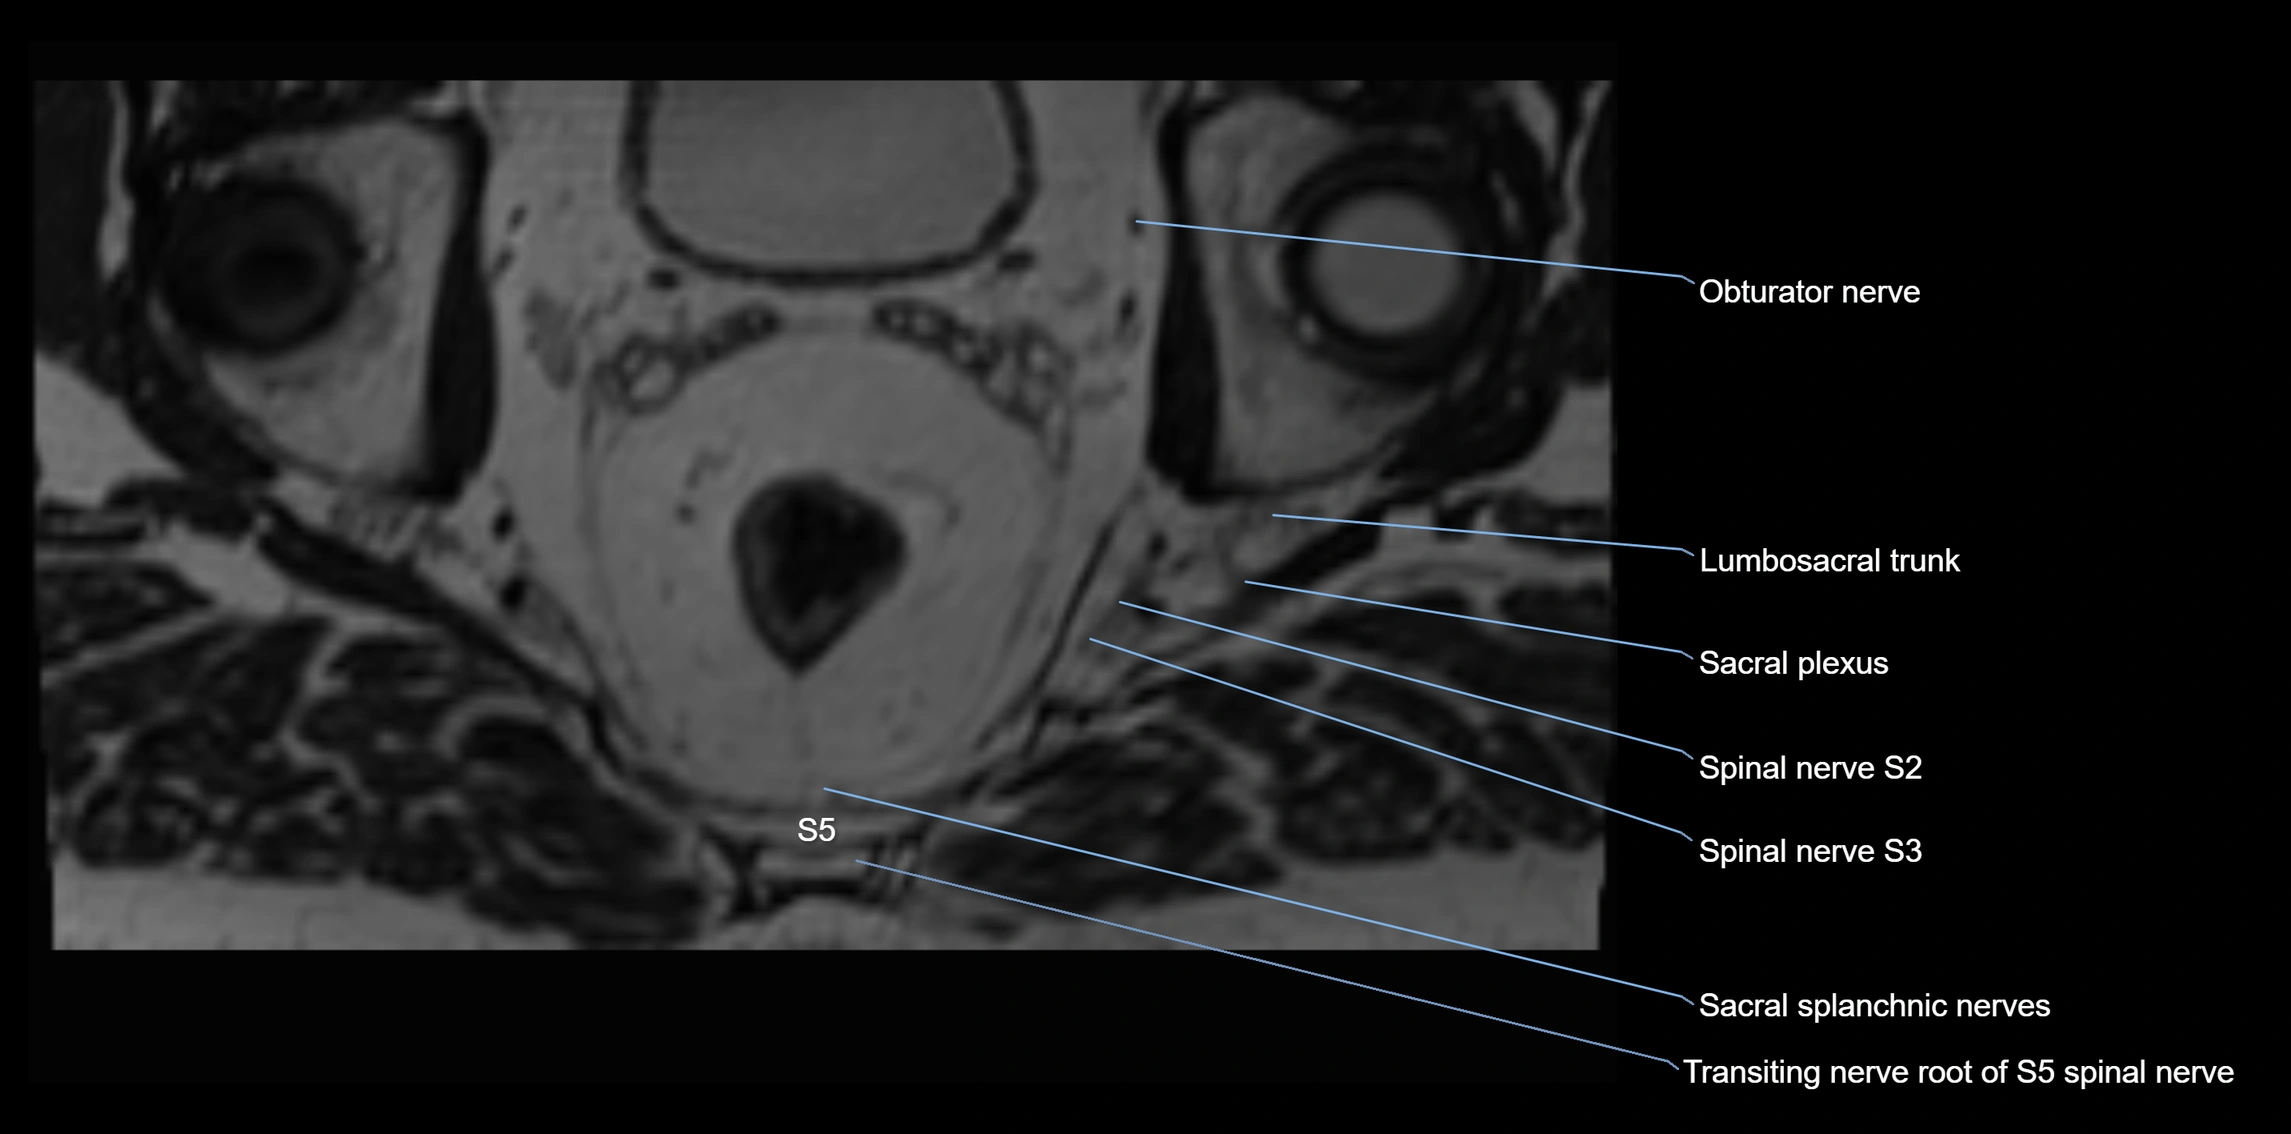

MRI image

image